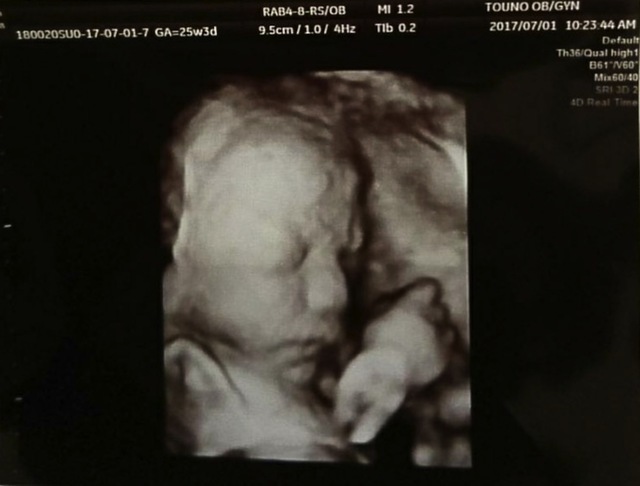

25週3日(25w3d・男の子)|ゆきぱ39 さん(28歳)

エコー写真撮影時のエピソード:

初めて4Dエコーで見たときの写真です。今までのエコーよりもくっきりと顔を見せてくれて、より愛おしさが増しました。早く会いたい気持ちも強まりました。

また産まれて来たら、この写真と見比べて見たいです。産まれてくるのが楽しみで仕方がありません。